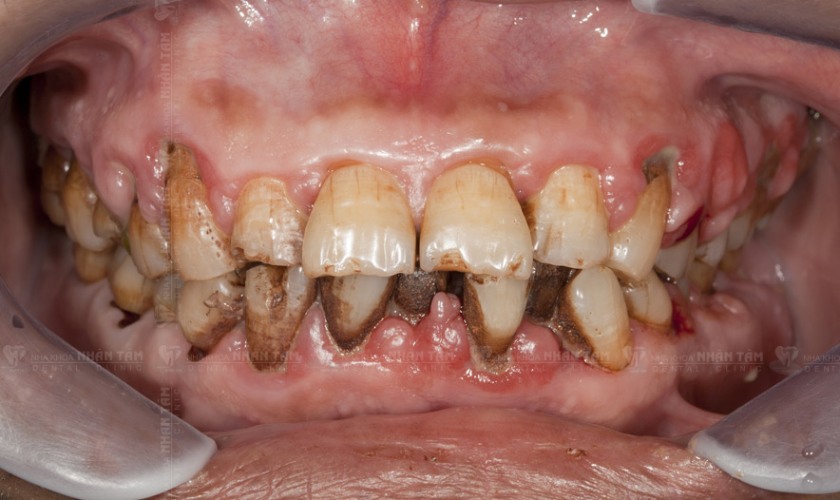

Tổn thương nướu răng kéo dài: Nướu sẽ bị sưng tấy, đỏ, có vết loét và lâu lành. Bệnh nhân có thể cảm thấy đau hoặc không, vùng niêm mạc xung quanh sẽ bị đổi màu, có thể chảy máu nướu.

Lung lay răng: Các tế bào ung thư xâm lấn và phá hủy mô nướu, mô nha chu và mô xung quanh chân răng, khiến chân răng trở nên lỏng lẻo và lung lay theo thời gian. Biểu hiện này khá giống với bệnh viêm nha chu, nên nhiều bệnh nhân thường hay nhầm lẫn.

Việc chăm sóc răng kém khoa học và vệ sinh răng miệng kém sẽ khiến mảng bám vi khuẩn bám trên răng, trong kẽ răng và bên trong viền nướu. Vi khuẩn sinh sôi sẽ phá hủy cấu trúc mô nướu và làm tăng tỷ lệ bị ung thư nướu răng.